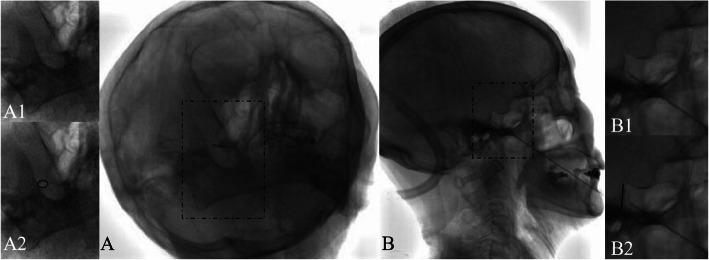

The patient was a 78-year-old man with the chief complaint of a 3-month history of PHN secondary to RHS with polycranial nerve (V, VII, VIII, and IX) involvement. Multimodality therapy with oral gabapentin, pulsed radiofrequency (PRF) application to the Gasserian ganglion for pain in the trigeminal nerve region, linear-polarized near-infrared light irradiation for pain in the facial nerve region, and 2% lidocaine spray for pain in the glossopharyngeal nerve region was used to the treat patient, and follow-up evaluations included thermography. This comprehensive treatment obviously improved the quality of life, resulting in considerable pain relief, as indicated by a decrease in the numerical rating scale (NRS) score from 9 to 3 and a decrease in thermal imaging temperature from higher to average temperature on the ipsilateral side compared with the contralateral side. Lidocaine spray on the tonsillar branches of the glossopharyngeal nerve resulted in an improvement in odynophagia, and the NRS score decreased from 9 to 0 for glossopharyngeal neuralgia after three applications.

Although the use of thermography in the follow-up of RHS with multiple cranial nerve (V, VII, VIII, and IX) involvement is very rare, in this patient, thermal imaging showed the efficacy of combination therapy (oral gabapentin, 2% lidocaine sprayed, PRF application and linear-polarized near-infrared light irradiation) and that is a good option for treatment.